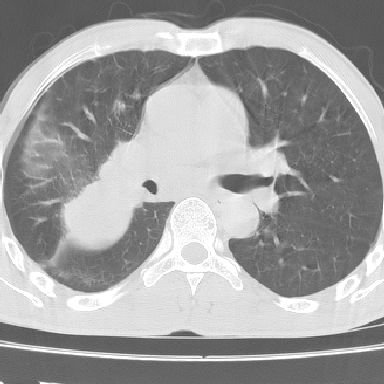

以下是引用lpc0ct在2006-11-28 16:12:00的发言:[br]大家图文并貌分析的太全面了,没有可说的,同意 [br] 右肺上叶中心型肺癌伴肺门、纵隔淋巴结转移.[br]

以下是引用dyqct在2006-11-28 16:00:00的发言:[br]右肺上叶中心型肺癌伴肺门、纵隔淋巴结转移。[br][br]